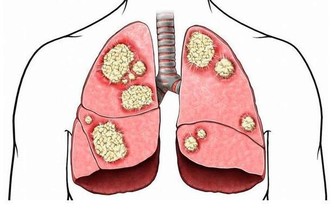

現代醫學界發現,免疫力與衰老有密切關係,免疫力減退是導致衰老的因素之一。並且,醫學界還越來越傾向於,提高免疫力能夠抑制腫瘤發生,預防腫瘤復發和轉移,對於癌症患者有重大意義。

而免疫系統,是人體自身的防禦機制,它最大的作用在於識別和消滅外來入侵的異物(包括病毒、細菌等),同時處理衰老、損傷等自身細胞(包括受感染或癌變的細胞),從而保護人們遠離疾病,讓人們保持年輕。